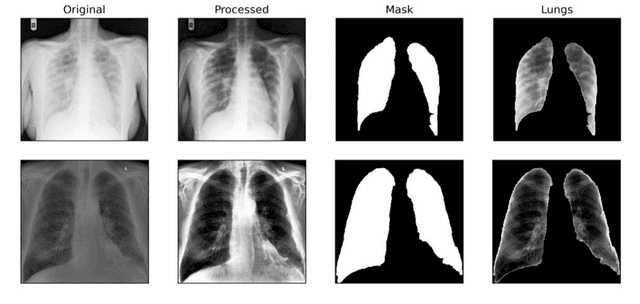

Abstract:Background and Objective: Artificial intelligence (AI) methods coupled with biomedical analysis has a critical role during pandemics as it helps to release the overwhelming pressure from healthcare systems and physicians. As the ongoing COVID-19 crisis worsens in countries having dense populations and inadequate testing kits like Brazil and India, radiological imaging can act as an important diagnostic tool to accurately classify covid-19 patients and prescribe the necessary treatment in due time. With this motivation, we present our study based on deep learning architecture for detecting covid-19 infected lungs using chest X-rays. Dataset: We collected a total of 2470 images for three different class labels, namely, healthy lungs, ordinary pneumonia, and covid-19 infected pneumonia, out of which 470 X-ray images belong to the covid-19 category. Methods: We first pre-process all the images using histogram equalization techniques and segment them using U-net architecture. VGG-16 network is then used for feature extraction from the pre-processed images which is further sampled by SMOTE oversampling technique to achieve a balanced dataset. Finally, the class-balanced features are classified using a support vector machine (SVM) classifier with 10-fold cross-validation and the accuracy is evaluated. Result and Conclusion: Our novel approach combining well-known pre-processing techniques, feature extraction methods, and dataset balancing method, lead us to an outstanding rate of recognition of 98% for COVID-19 images over a dataset of 2470 X-ray images. Our model is therefore fit to be utilized in healthcare facilities for screening purposes.